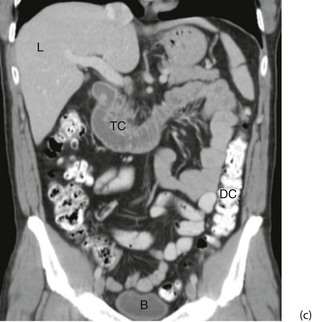

Principles of magnetic resonance imaging: Magnetic resonance imaging (MRI) was introduced into clinical practice in the early 1980s. MRI involves applying a powerful magnetic field to the body which causes the protons of hydrogen nuclei to become aligned. The protons are then excited by pulses of radio waves transmitted at a frequency that causes them to resonate and emit radio signals; these are recorded electronically. Sophisticated computation then produces images which can be viewed in any plane, transversely, longitudinally or at any obliquity (see Fig. 5.11).

Fig. 5.11 Magnetic resonance images

(a) Gadolinium enhanced T1-weighted coronal MRI of the brain. Note enhancement of a tumour T, midline shift with compression of the right lateral ventricle L. The falx F and third ventricle 3 are also labelled. (b) T1-weighted sequence sagittal MRI of the thoracic spine in a patient with known prostate cancer, back pain and an elevated prostate specific antigen. The image demonstrates bony metastases as dark areas in the vertebral bodies and spines; the white areas are normal fat in the marrow

Lipids have particularly high hydrogen content and are clearly seen on MRI. For this reason, the initial applications of MRI were in examining the brain and spinal cord. The technique is increasingly employed for investigating joints such as the knee, shoulder, hip and ankle, and in some cases replaces the need for arthroscopy. Examination times have fallen and good-quality images of chest, abdomen and pelvis can now be obtained. However, MRI is unsuitable for imaging gas-filled organs and dense bone.